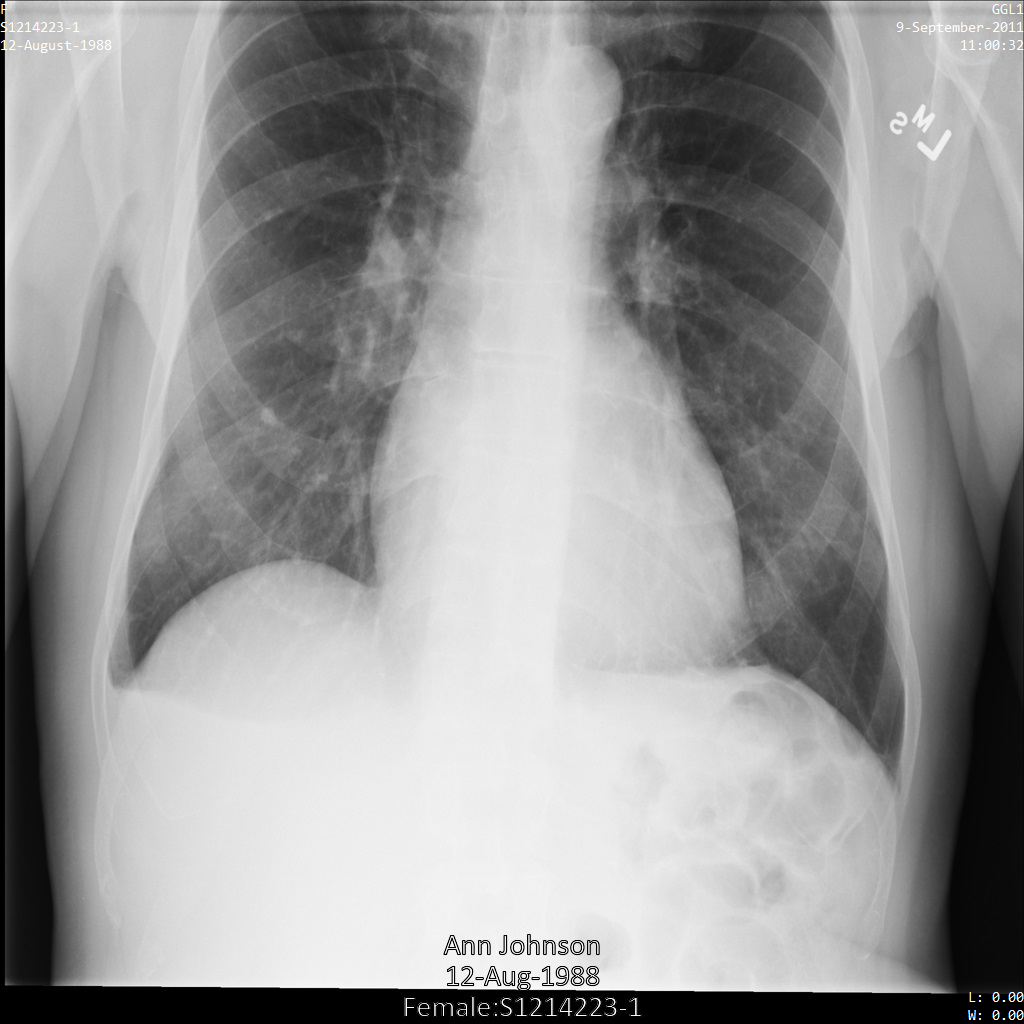

Setiap bagian berikut memberikan contoh cara melakukan de-identifikasi data DICOM menggunakan berbagai metode. Output gambar yang tidak diidentifikasi disediakan dengan setiap sampel. Setiap sampel menggunakan gambar asli berikut sebagai input:

Anda dapat membandingkan gambar output dari setiap operasi penghapusan identitas dengan gambar asli ini untuk melihat efek operasi.

Setelah mengirimkan gambar ke Cloud Healthcare API, gambar akan muncul seperti berikut. Meskipun metadata yang ditampilkan di sudut atas gambar telah disamarkan, informasi kesehatan terlindungi (PHI) yang tercetak di bagian bawah gambar tetap ada. Untuk juga menghapus teks sisipan, lihat Menyamarkan teks sisipan dari gambar.

REST